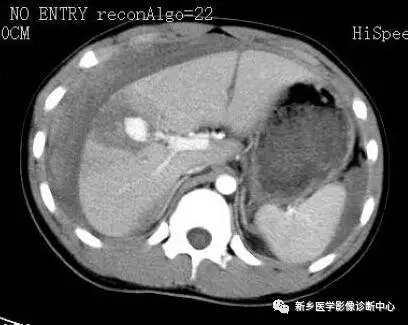

13 肠梗阻

文章图片

1.肠梗阻:中腹部多发阶梯状 , 马蹄状液平 。 2.空肠不全性梗阻 。

1.空肠不全性梗阻:空肠扩展呈弹簧状 。 2.空肠机械性梗阻:弹簧征